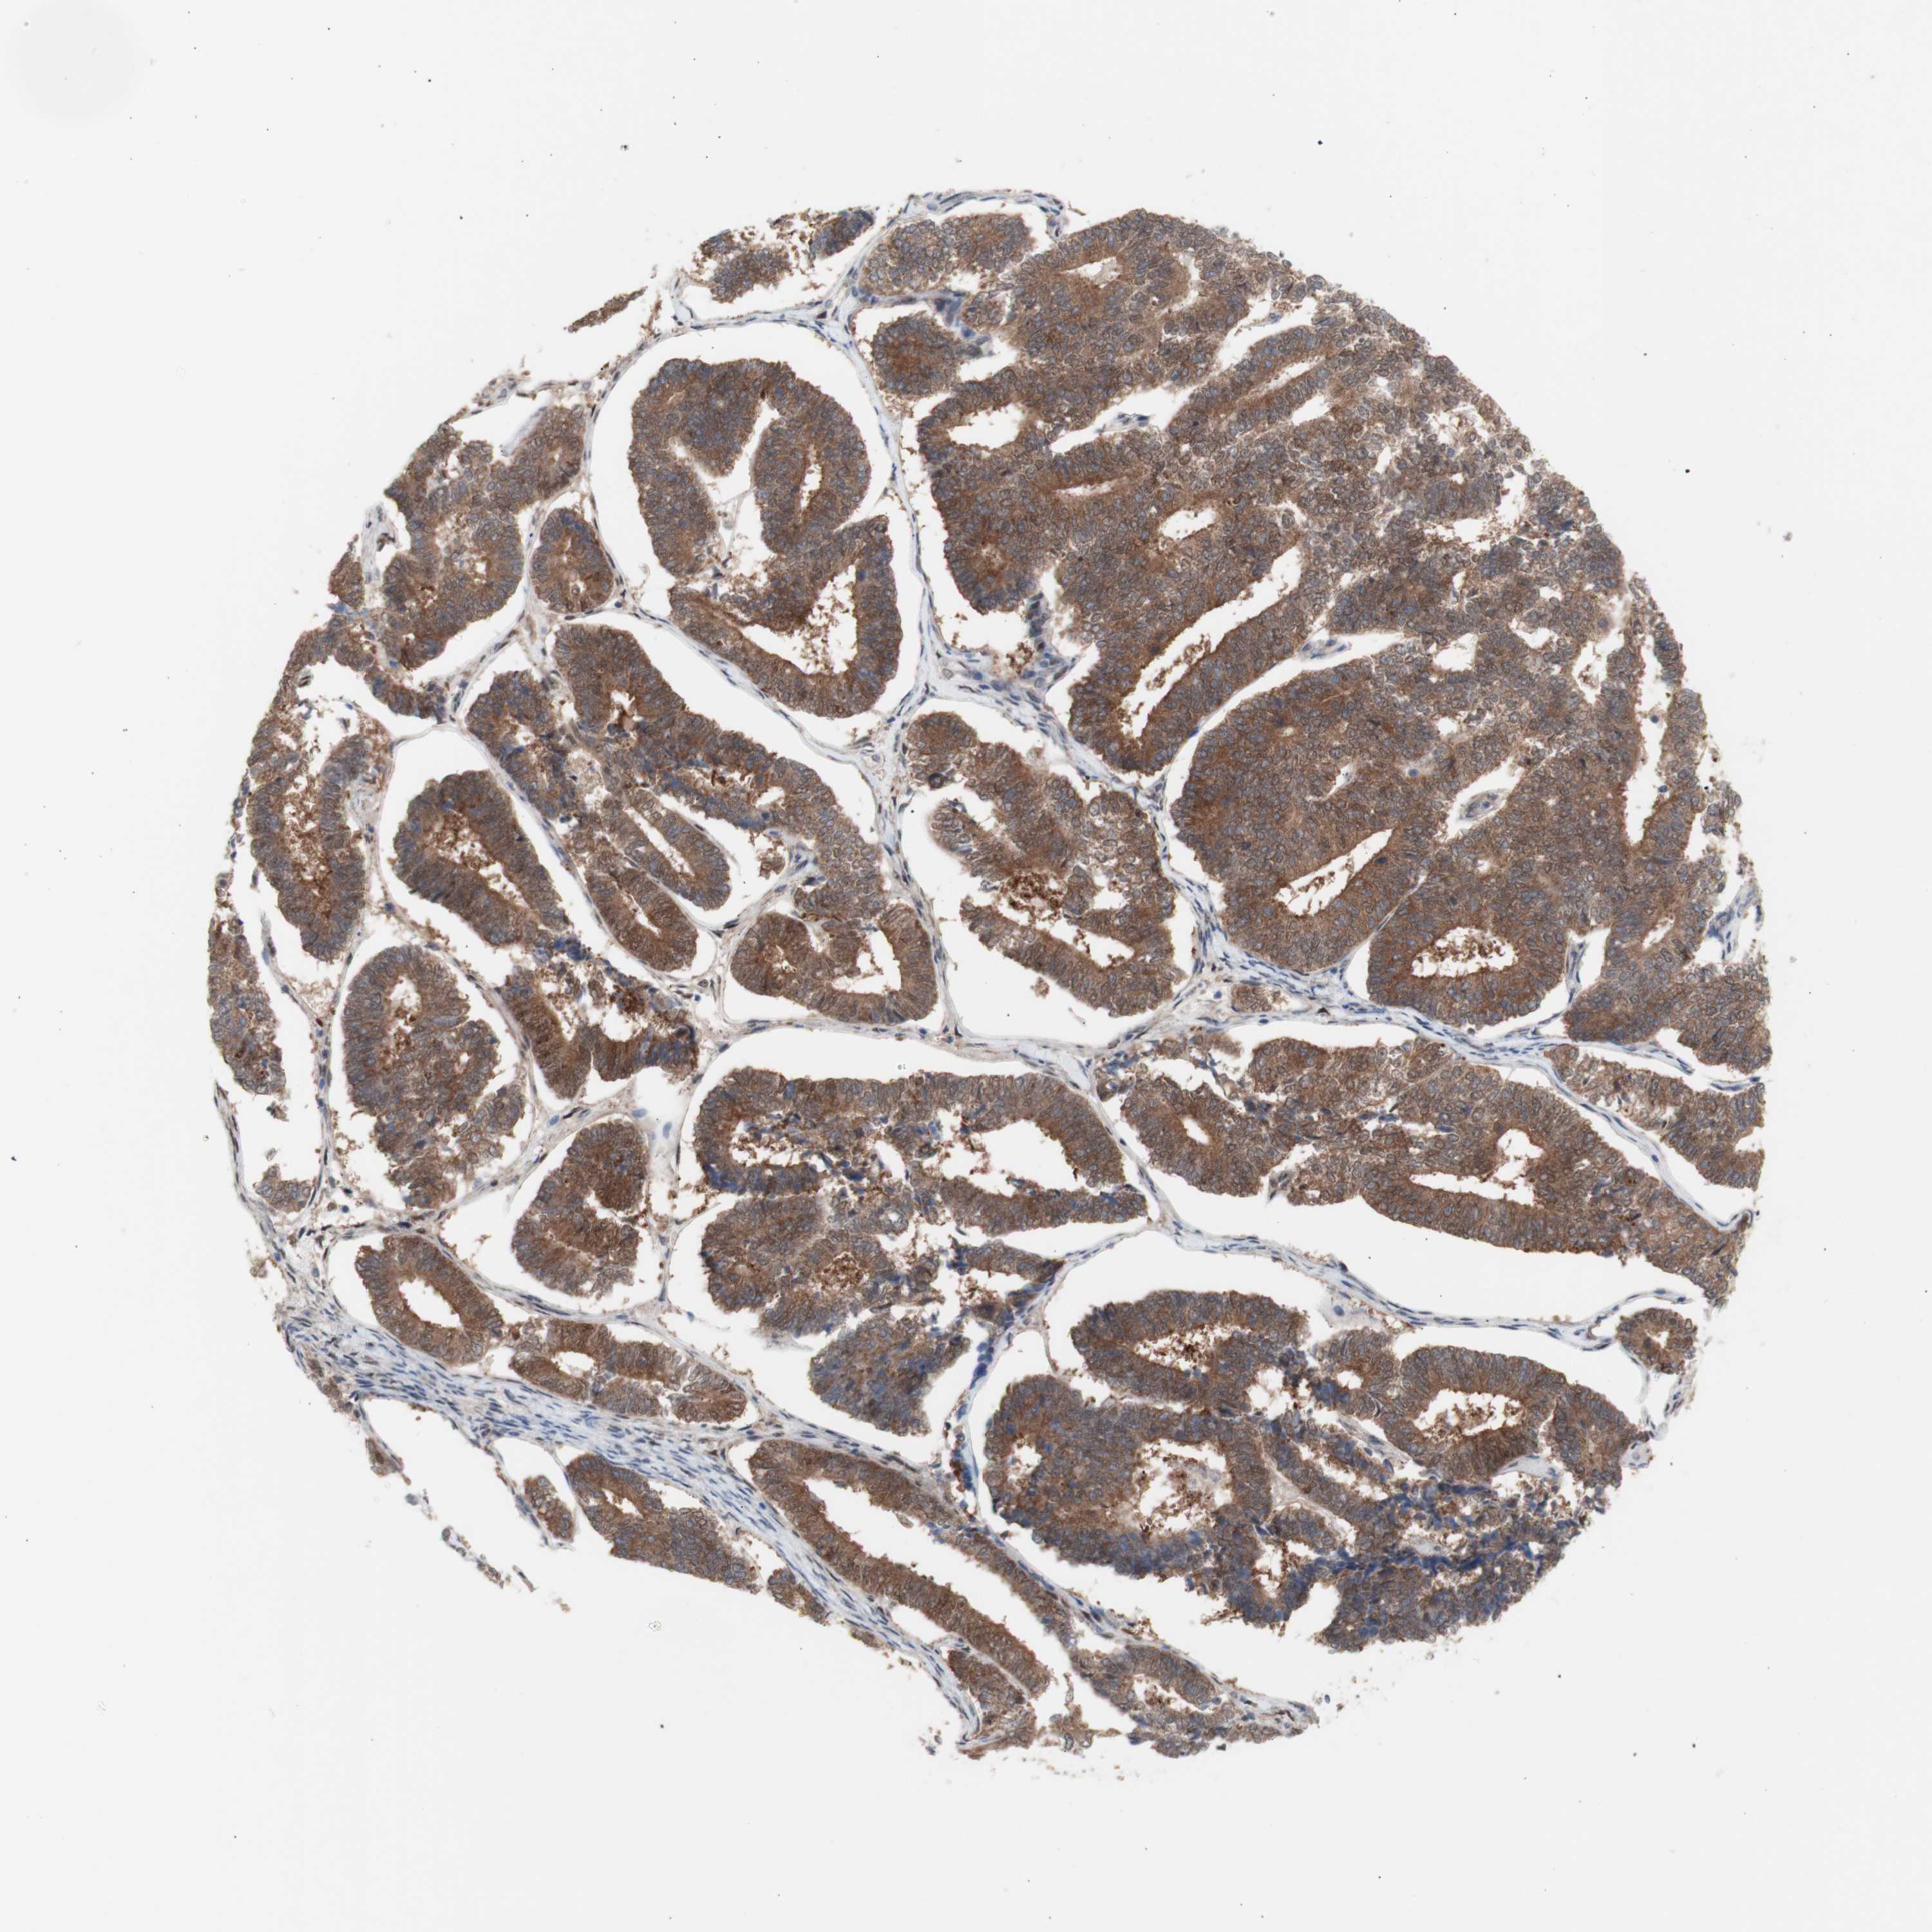

ENDOMETRIAL CANCER - Protein expressioni

A mouse-over function shows sample information and annotation data. Click on an image to view it in a full screen mode. Samples can be filtered based on level of antibody staining by selecting one or several of the following categories: high, medium, low and not detected. The assay and annotation is described here.

Note that samples used for immunohistochemistry by the Human Protein Atlas do not correspond to samples in the TCGA dataset.

Antibody stainingi

Antibody staining in the annotated cell types in the current human tissue is reported as not detected, low, medium, or high, based on conventional immunohistochemistry profiling in selected tissues. This score is based on the combination of the staining intensity and fraction of stained cells.

Each image is clickable and will lead to virtual microscopy that enables deeper exploration of all samples and also displays staining intensity scores, fraction scores and subcellular localization as well as patient and tissue information for each sample.

Antibody HPA005525

Antibody HPA064708

Antibody CAB012459

Staining

High

Medium

Low

Not detected

Intensity

Strong

Moderate

Weak

Negative

Quantity

>75%

75%-25%

<25%

None

Location

Nuclear

Cytoplasmic/membranous

Cytoplasmic/membranous,nuclear